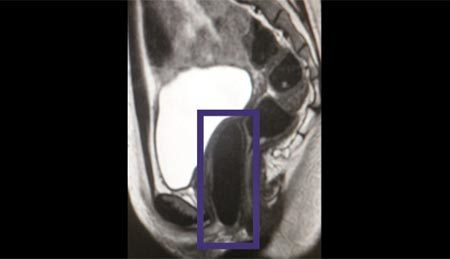

| Ảnh chụp cộng hưởng từ cho thấy âm đạo nhân tạo bên trong cơ thể bệnh nhân. Ảnh: CNN |

Theo các nhà nghiên cứu đến từ Viện Y học tái sinh thuộc Trung tâm Y tế Wake Forest (Mỹ), 4 nữ bệnh nhân vị thành niên đã được cấy ghép thành công các âm đạo nhân tạo phát triển từ chính tế bào của họ. Ở thời điểm diễn ra các cuộc phẫu thuật từ tháng 6/2005 đến tháng 10/2008, các bệnh nhân đang trong độ tuổi từ 13 - 18.

Toàn bộ dữ liệu theo dõi thường niên, tới tận 8 năm sau phẫu thuật cho thấy, các bộ phận sinh dục nhân tạo đều hoạt động bình thường. Viết trên tạp chí The Lancet, tiến sĩ Anthony Atala, người đứng đầu dự án, tuyên bố: "Nghiên cứu thử nghiệm này là công trình đầu tiên cho thấy, âm đạo có thể được nuôi cấy trong phòng thí nghiệm và sử dụng ở người".